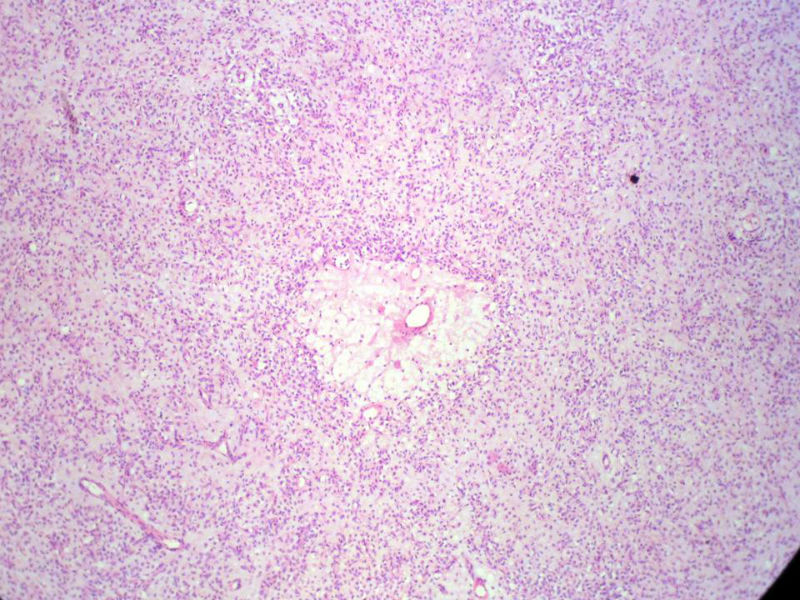

男,27岁,右股骨上段皮下肿物1年余,无明显疼痛,检查肿物明显隆起于皮下,边界清楚,手术完整切除肿物。肉眼,肿物6X6X5厘米,外观多结节状,似有包膜,切面灰白色,质韧。

特别提示:镜下核分裂3-4/HP.

3. 本例组织学改变与粘液性脂肪肉瘤,粘液样纤维肉瘤,纤维粘液样肉瘤,骨外粘液样软骨肉瘤都有重叠之处,且镜下并未见典型结构。由此,免疫组化结果就尤显重要。特别是专业书籍提到,突触素或嗜铬素阳性,对鉴别诊断有重要意义。我用CGA,也是在以上几个肿瘤中举棋不定而为。NSE和CK没用,其实我想用更多的抗体来证实更多的东西,但患者的经济条件不太好,遗憾!